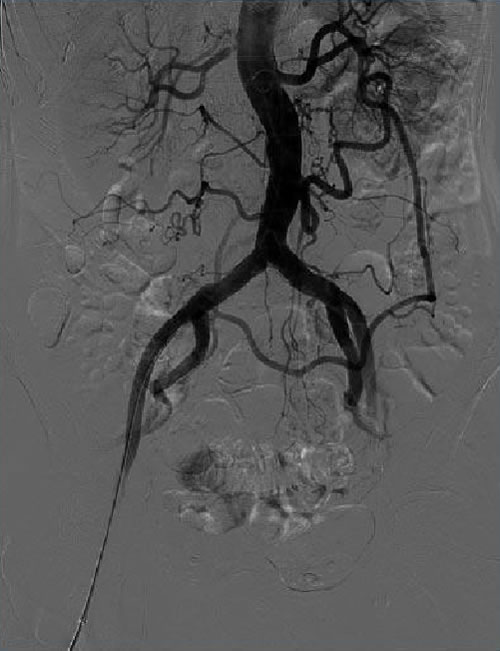

To confirm the diagnosis, a renal artery duplex ultrasound is performed. This confirms the diagnosis, estimates the degree of stenosis and provides information about the success of any intervention to the kidney. If there are difficulties encountered with performing the duplex ultrasound, further imaging is required, Computed Tomography-Angiogram (CTA), Magnetic Resonant-Angiogram (MRA) or formal renal angiogram is considered.

Depending on the presentation, management may involve revascularisation of the renal artery. Revascularisation means improving the blood supply to the kidney. This is often performed with minimally invasive techniques with ballooning +/- stent however, much less commonly, open surgery may be required.

Diagnosis is confirmed with duplex ultrasound. If confirmed, further imaging with CT-Angiography or MR-Angiography or formal angiogram is performed to plan revascularisation. Surgical intervention is aimed to improve the blood supply to the bowel (revascularisation). Options include minimally invasive techniques (balloon +/- stent) or less commonly, open surgery.